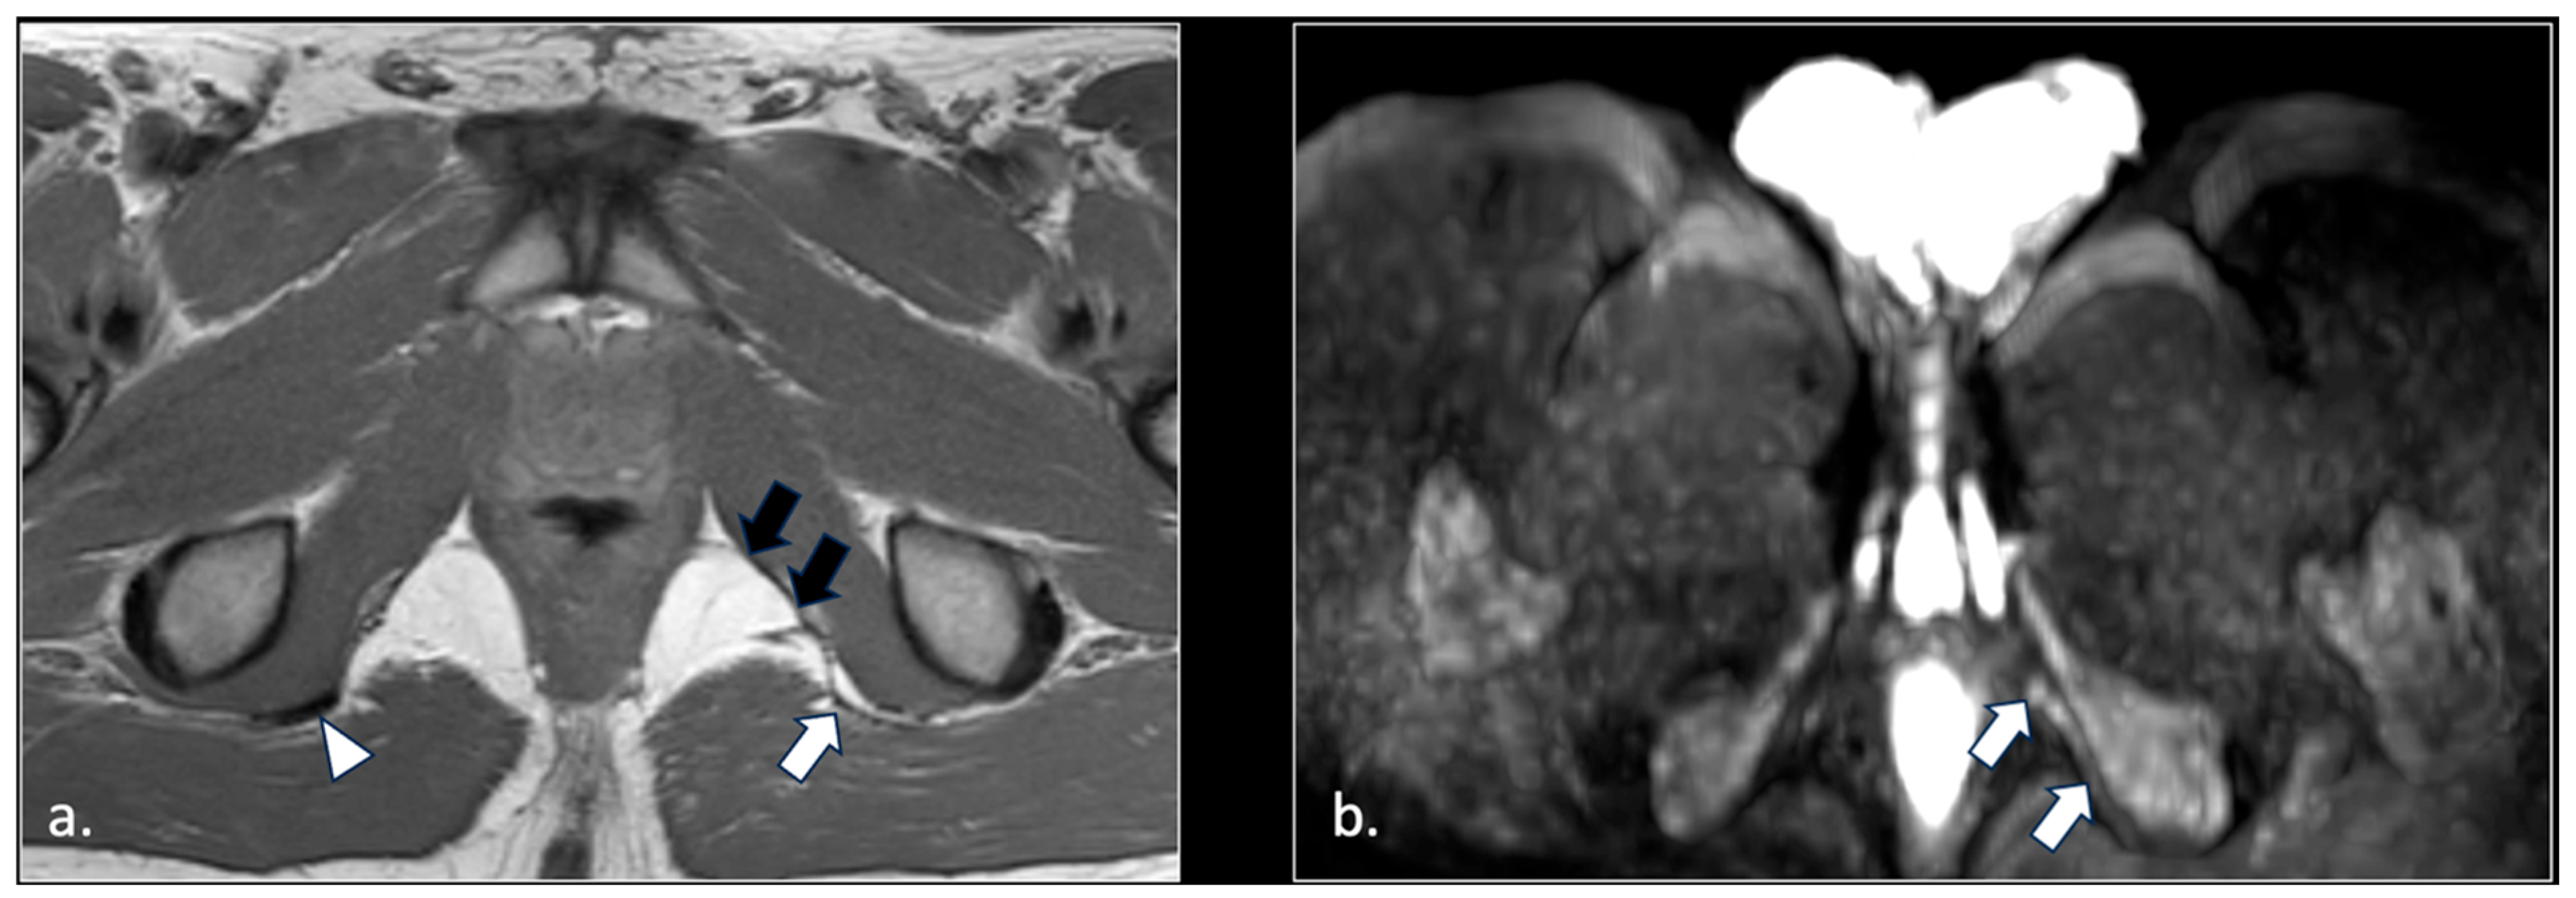

- Unilateral or bilateral lesions of the sacrotuberous and/or sacrospinous ligaments (interligamentous space) (5 patients);

- Unilateral rupture of puborectal and/or pubococcygeal muscle (4 patients);

- Perineal fibrosis involving Alcok’s canal (4 patients);